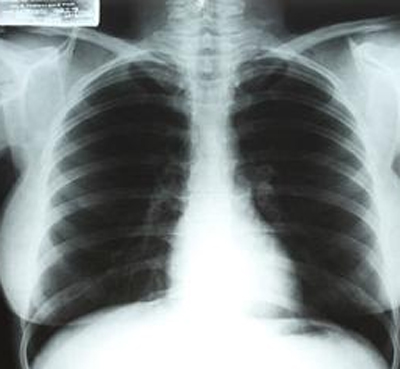

中新網(wǎng)4月14日電 據(jù)臺灣“今日新聞”消息,好萊塢性感女星瑪麗蓮.夢露生前的一張X光片即將舉行拍賣。

報道稱,這張X光片是1954年時,夢露在洛杉磯Cedars of Lebanon醫(yī)院里拍下的。據(jù)悉,此張X光片可望以38萬4000美元左右的售價拍賣出去。

此次拍賣會定于6月26至27日在拉斯韋加斯的好萊塢星球賭場舉行。同時拍賣的,還有夢露的一瓶尚未開封的香奈兒5號香水;一本拍電影時的筆記本,以及一件粉紅色絲質(zhì)襯衫等。